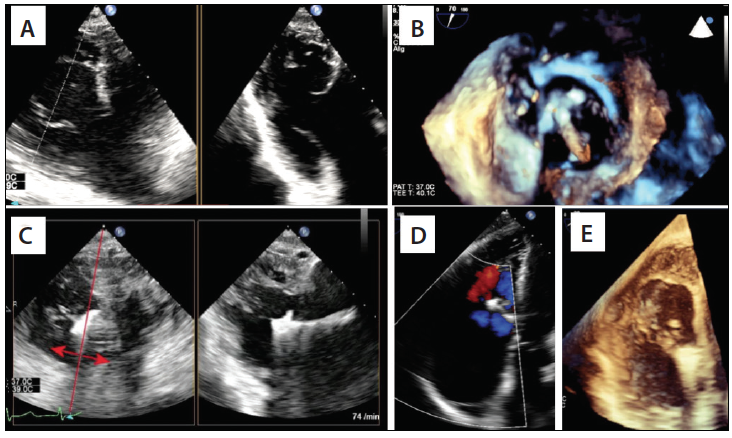

Echocardiographic Guidance of the MitraClip Procedure for TR Repair

Similar to MR repair, the most frequently used device to repair TR is the off-label use of the MitraClip device. Two-dimensional TEE is a mandatory imaging modality for evaluating the suitability for TR edge-to-edge repair. Two-dimensional TEE biplane imaging with the primary view displaying the right ventricular inflow-outflow view is paramount to identify the tricuspid leaflets and visualize the coaptation of the septal-anterior and septal-posterior commissure with the secondary perpendicular plane.17 A stepwise approach for TR edge-to-edge repair is summarized in Table 4 and Figure 3.

Figure 3. Stepwise intraprocedural imaging of the MitraClip procedure for TR. Biplane TEE transgastric view (A). Three-dimensional TEE image of clip positioning; the clip is positioned perpendicular to the closure line between the anterior and septal leaflet (B). Biplane TEE transgastric view guidance of clip positioning; continuous slight movement of the biplane beam from left to right in order to visualize both arms of the clip (C). TEE transgastric view (D). The final result after clipping (E).

Courtesy of Joachim Schofer, MD.